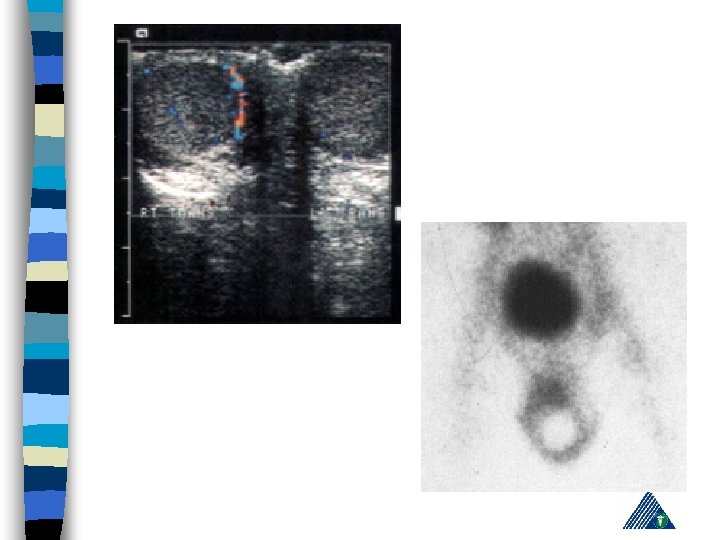

n n n Epidydimis may be palpated in an abnormal location – early sign Leucocytosis within a few hours Doppler US or nuclear scan Manuel de-torsion (inside out) (local anest) Eksploration !!! 5 -6 hrs